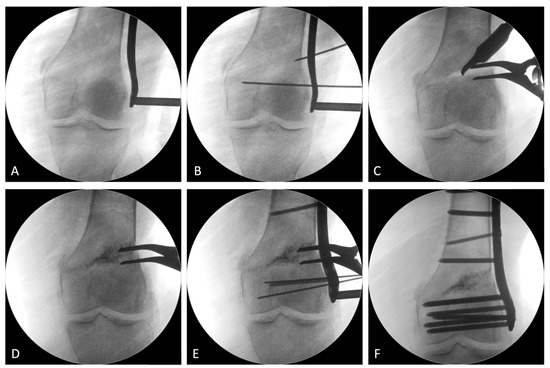

2.2. Surgical Procedure